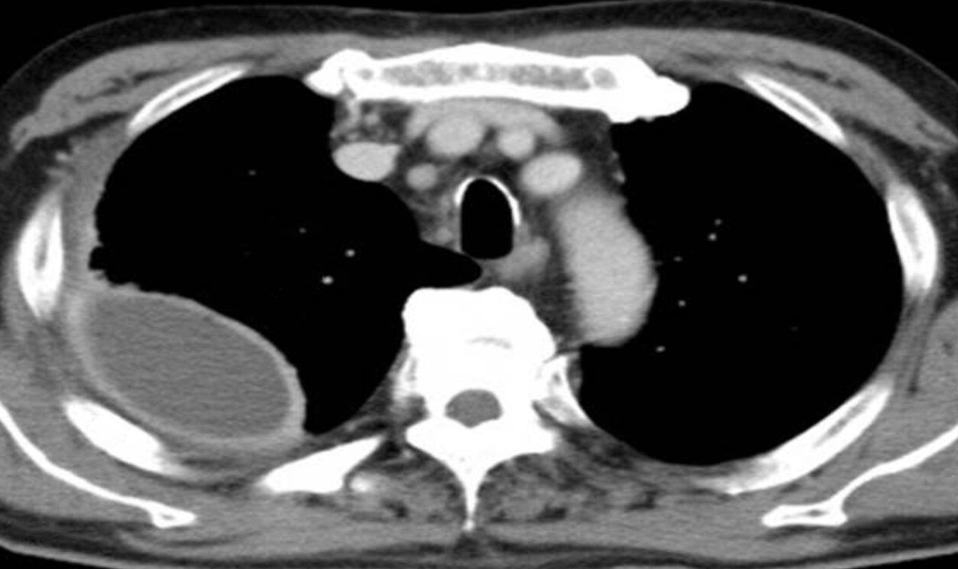

- CT thorax (with contrast; axial view)

- A mucosal flap can be seen dividing the lumen of the ascending and descending aorta.

- This radiological appearance confirms an aortic dissection.